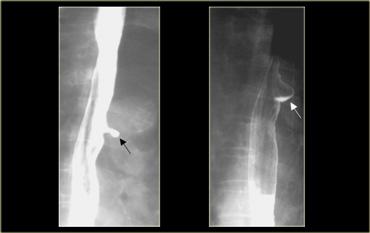

Bên trái là hình ảnh nam bệnh nhân 52 tuổi với triệu chứng nuốt khó từng đợt.

Hình ảnh ngoài cùng bên trái không cho thấy bất thường, tuy nhiên thực quản đoạn xa chưa giãn căng.

Khi thực quản đoạn xa giãn căng, vòng B Schatzki rộng 13 mm (các mũi tên) gây tắc nghẽn từng đợt được hiển thị rõ tại đỉnh của thoát vị hoành (đầu mũi tên).

Bên trái là hình ảnh nam bệnh nhân 71 tuổi với triệu chứng đau ngực sau bữa ăn nhanh.

Khiếm khuyết ngấm thuốc gây tắc nghẽn ở đoạn xa (mũi tên) là một mảnh thịt đã di chuyển vào dạ dày trong quá trình thăm khám.

Hình ảnh thực quản chụp theo dõi cho thấy vòng B Schatzki (các mũi tên) là nguyên nhân gây tắc nghẽn.